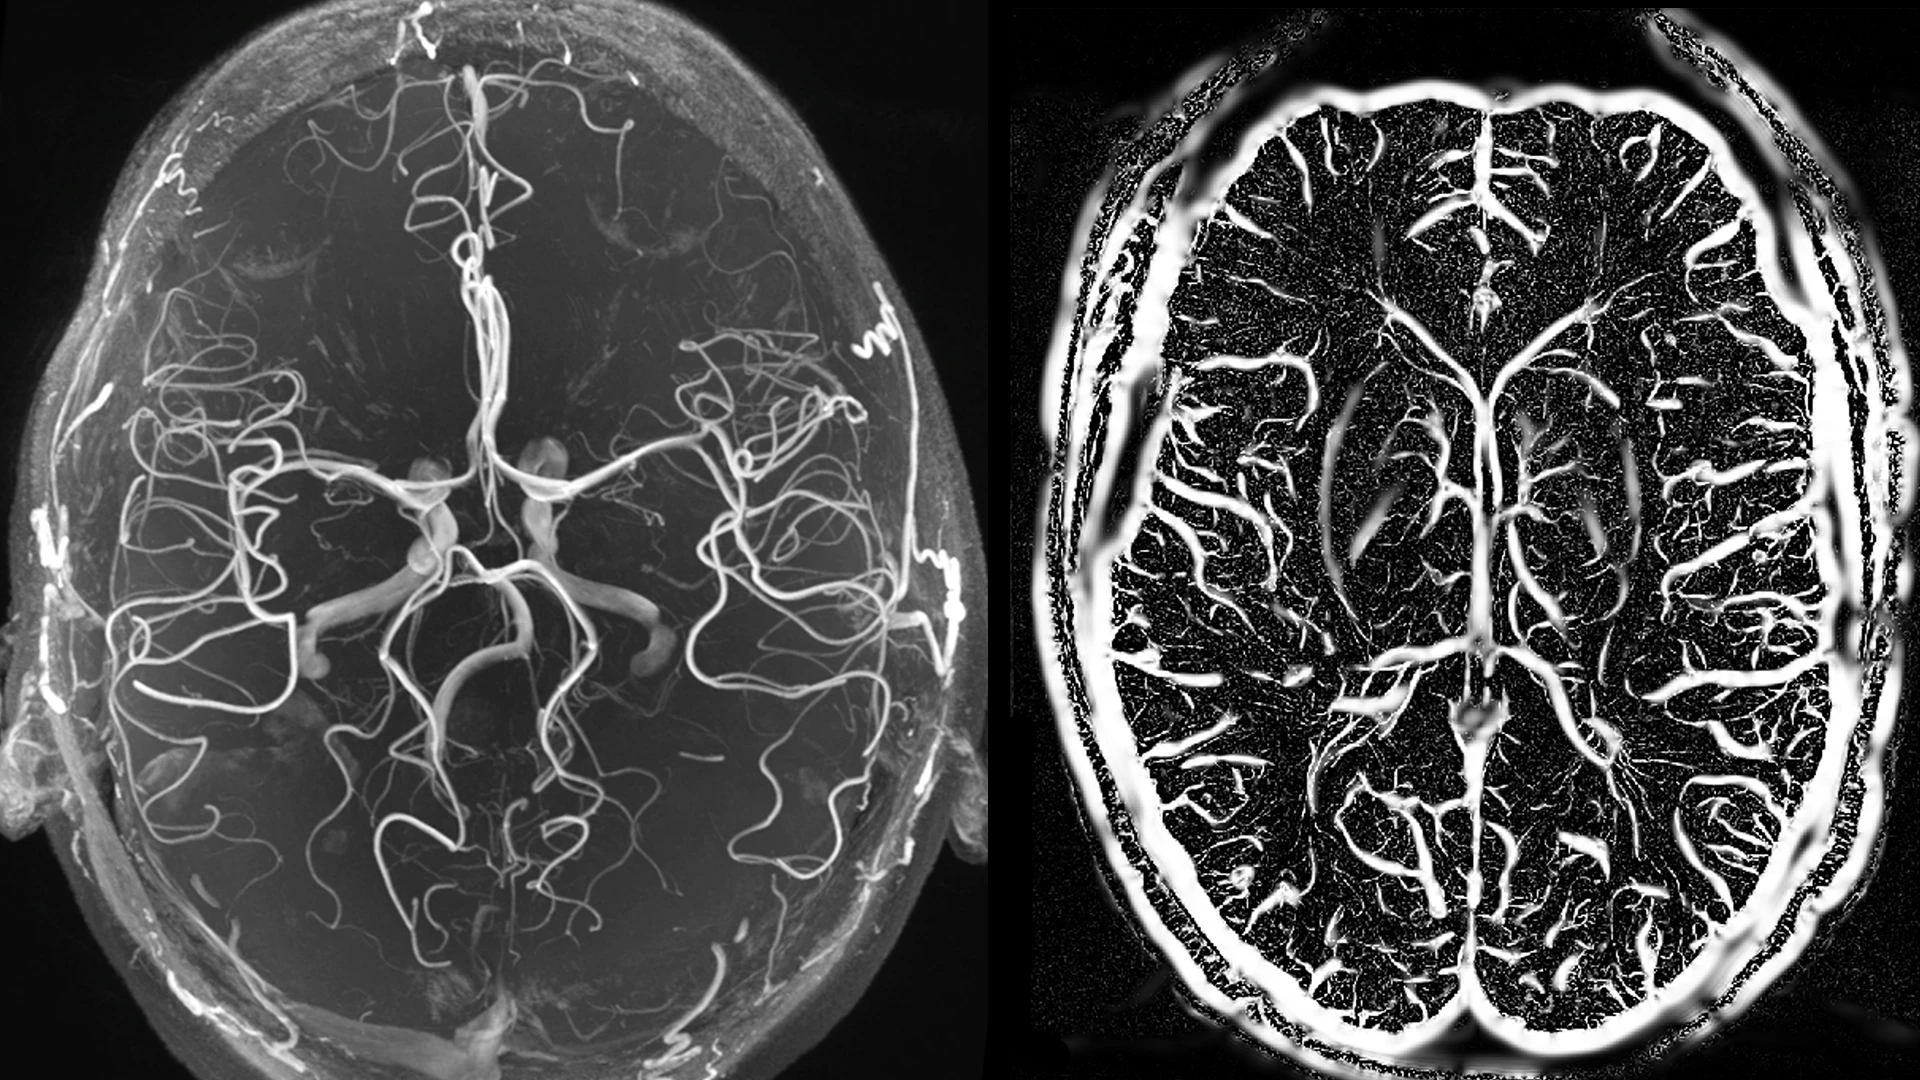

Figure 2. 7-T time of flight (TOF) image showing arteries (left) and SWI segmentation showing veins (right). This depicts 7-T TOF imaging and susceptibility-weighted imaging (SWI) allow visualization of vascular abnormalities that may underlie structural lesions.